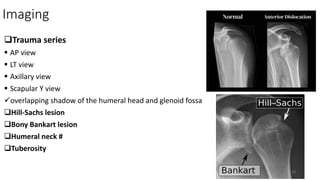

Imaging

Trauma series

 AP view

 LT view

 Axillary view

 Scapular Y view

overlapping shadow of the humeral head and glenoid fossa

Hill-Sachs lesion

Bony Bankart lesion

Humeral neck #

Tuberosity